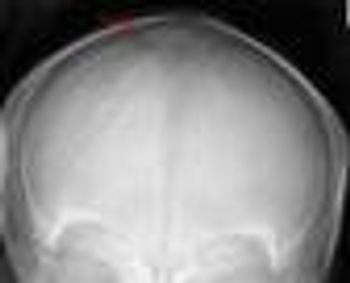

Wormian bones (anterior fontanellar bones) are extra islands of bone within the calvarial sutures of the skull.